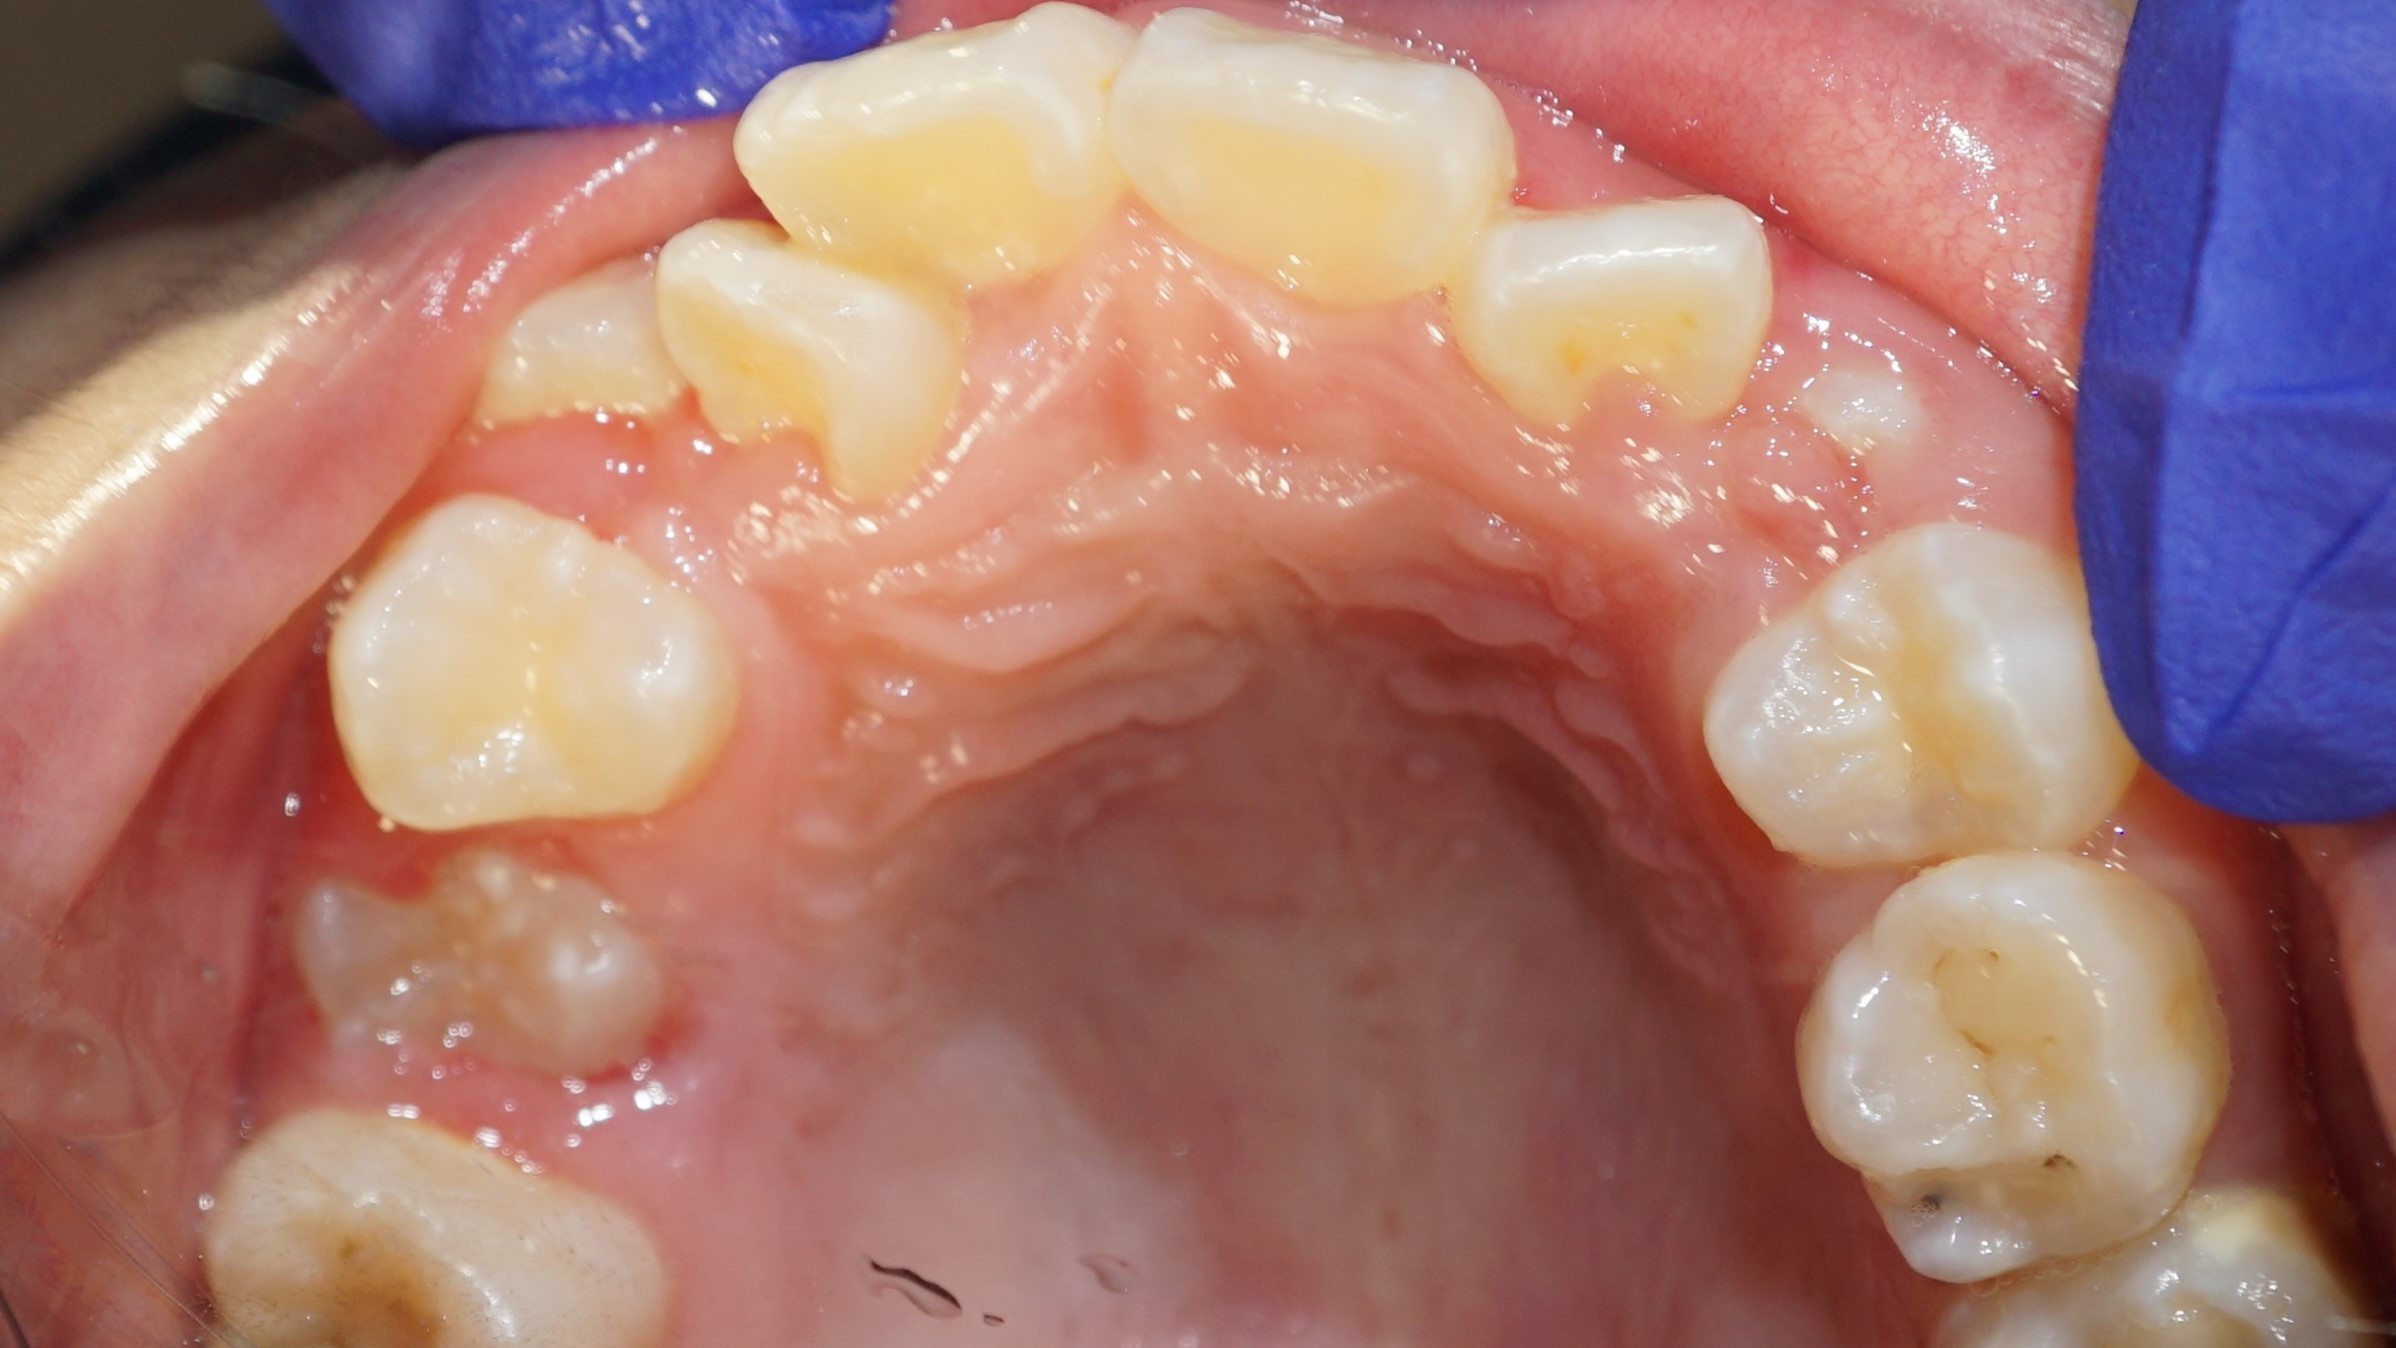

Before

After

Before

After

Before

After

Before

After